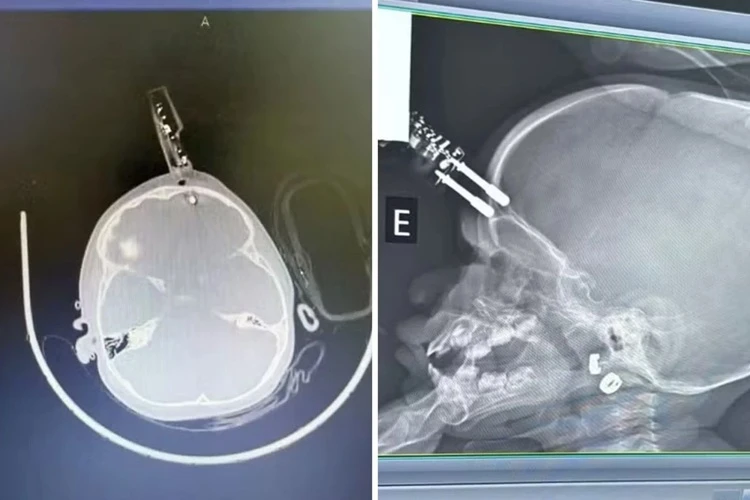

Bebê de um ano cai e fica com carregador de celular preso ao crânio Foto: Reprodução/G1

Uma bebê de um ano ficou com um carregador cravado na testa após cair da cama, na última terça-feira (13). A mãe da criança foi ao banheiro no momento do acidente, informou o médico que atendeu a menina, Bruno Castro, em entrevista ao G1. O caso aconteceu na cidade de Divinópolis, interior de Minas Gerais.

Ainda segundo ele, a bebê estava com o carregador na mão no momento da queda, o que fez com que o aparelho atingisse a cabeça e perfurasse a região frontal do crânio.

A criança passou por uma cirurgia de urgência para retirada do objeto e reconstrução da área atingida. O médico acrescentou que ela segue internada e recebe antibiótico profilático. Ele também revelou que a paciente não apresenta sinais de sequelas.

“Crianças têm uma plasticidade neuronal muito boa, o que aumenta as chances de recuperação sem sequelas”, acrescentou em entrevista ao G1. Ainda assim, a menina vai passar por acompanhamento neurológico contínuo em caso de problemas futuros.